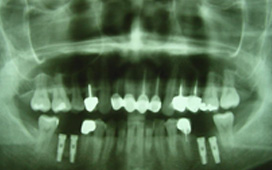

全口重建 / 植牙 ( 缺牙重建的設計考慮 )

缺一顆牙時,製作牙橋或放置一單顆植體的差別 缺牙的處理,一般有兩種方式,一是製作牙橋,另一是放置人工植牙。 牙橋的好處是製作時間快,費用可能較節省 ( 因為材質不同而有不同 ),費用大約在兩三萬附近,若含黃金比例高有可能高達6 - 7萬元 ; 但是缺點就是要修磨旁邊的牙齒,比較可惜,而且一旦是假牙,就終身是假牙,而重建的咬合也較差 ( 兩人做三人的工作 ) ,因為仍舊是少一個牙根,不過仍比不做好。 放人工牙根,也就是植牙,其最大好處就是不用修磨旁邊的牙齒,這一點其實是無價,而且完成後的咬合功能很好,幾乎和自然牙一樣,但植牙的費用較牙橋高,一顆植牙費用大約是六萬多塊到八九萬塊,會因為使用廠牌和有沒有補骨頭而有費用高低之不同,但植牙的使用年限較長,同時可避免周圍的骨頭繼續減少 ; 若照顧良好,也可能好幾十年,一般而言,十年的成功率有百分之八九十,算是非常高 ; 植牙因為要等骨頭和植體長牢,所以需要一些時間,一般上顎的牙要五、六個月,下顎因骨頭較為緻密,所以只需三四個月,但以長期的健康考慮,幾個月其實很快;以專業的建議,植牙確實比較好。

植體設計

寬直徑 vs 一般直徑